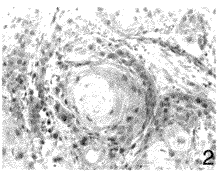

相鄰的棘細胞以橋粒相接。靠近淺層的棘細胞逐漸變成扁平形。棘細胞的細胞核位於中央,呈圓形或卵圓形,細胞質較豐富,嗜鹼性。電鏡觀察,有很多粗大的排列不規則的張力細絲,附著在橋粒的附著板上。此外,還有少量的卵圓形的膜被顆粒(membramecoating granules)。 棘細胞癌

是從表皮的棘細胞發生的皮膚癌這種癌的特徵是發生在面部、手腳等暴露部位,有各種各樣的癌前病變。所謂癌前病變包括有作為誘因的燒傷和外傷後的瘢痕、放射線損害、日光性角化病、鮑溫(Bowen)病、慢性炎症、化膿性肉芽腫和化學物質等。但是原因不明的也有不少。